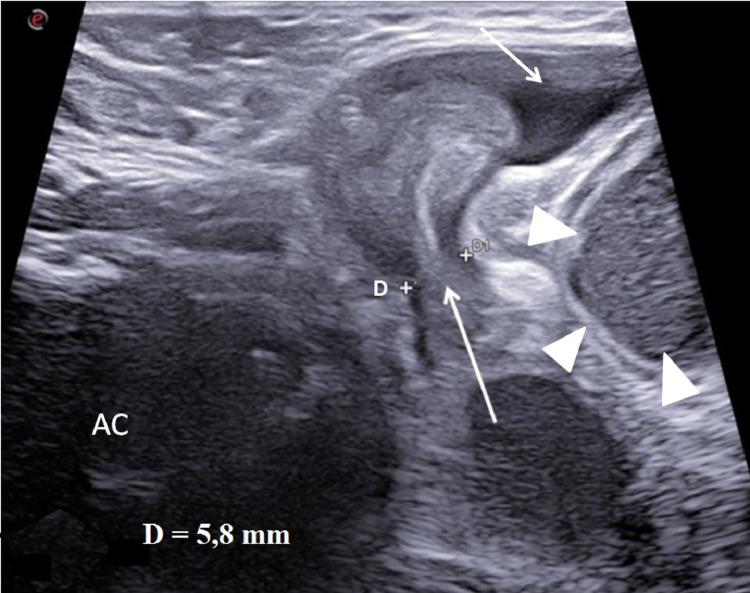

The Spigelian hernia is a abdominal wall hernia that originates from a discontinuity of the Spigelian fascia located lateral to the rectus abdominis muscle. It can be acquired in adults or congenital in newborns. In very rare cases in male it can be associated with cryptorchidism, in which case it is known as "Spigellian-Cryptorchidism Syndrome". It can be clinically highlighted with abdominal swelling wall along the semilunar line and intestinal obstruction. The diagnosis, as in all pediatric emergencies, must be timely and the method of choice is ultrasound which allows a rapid localization of the hernia breach and herniated structures. The treatment of choice is surgical with herniopexy and repositioning of the testicle into the scrotal sac, or orchipessy in cases of testicular necrosis. We describe ultrasound characteristics of Spigellian-cryptorchidism syndrome presenting with acute intestinal obstruction in a newborn.

半月线疝是一种腹壁疝,起源于腹直肌外侧的半月线筋膜连续性中断。它在成人中可能后天形成,在新生儿中可能是先天性的。在男性中,非常罕见的情况下它可能与隐睾症相关,在这种情况下被称为“半月线 - 隐睾症综合征”。临床上可表现为沿半月线的腹壁肿胀和肠梗阻。与所有儿科急症一样,诊断必须及时,首选方法是超声检查,它可以快速定位疝口和疝出结构。首选治疗方法是手术,进行疝修补术并将睾丸复位至阴囊,或在睾丸坏死的情况下进行睾丸固定术。我们描述了一名新生儿半月线 - 隐睾症综合征伴急性肠梗阻的超声特征。